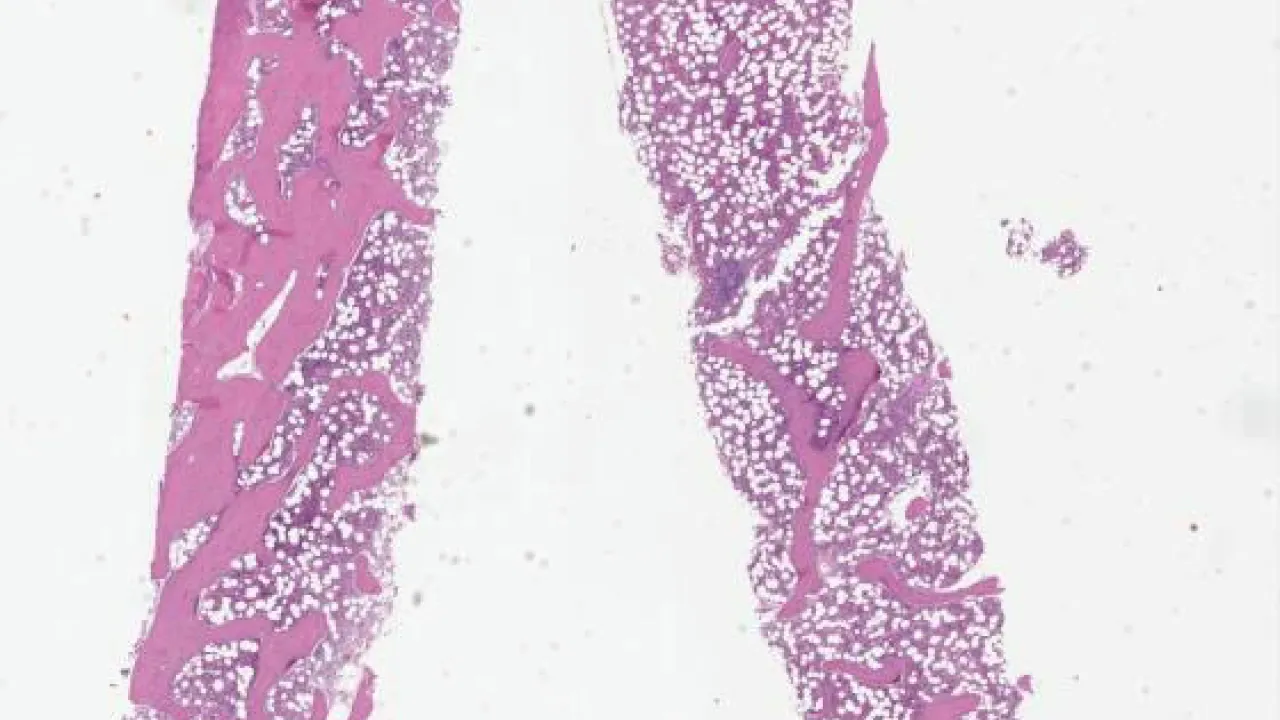

Bone Marrow, systemic mastocytosis, H&E stain